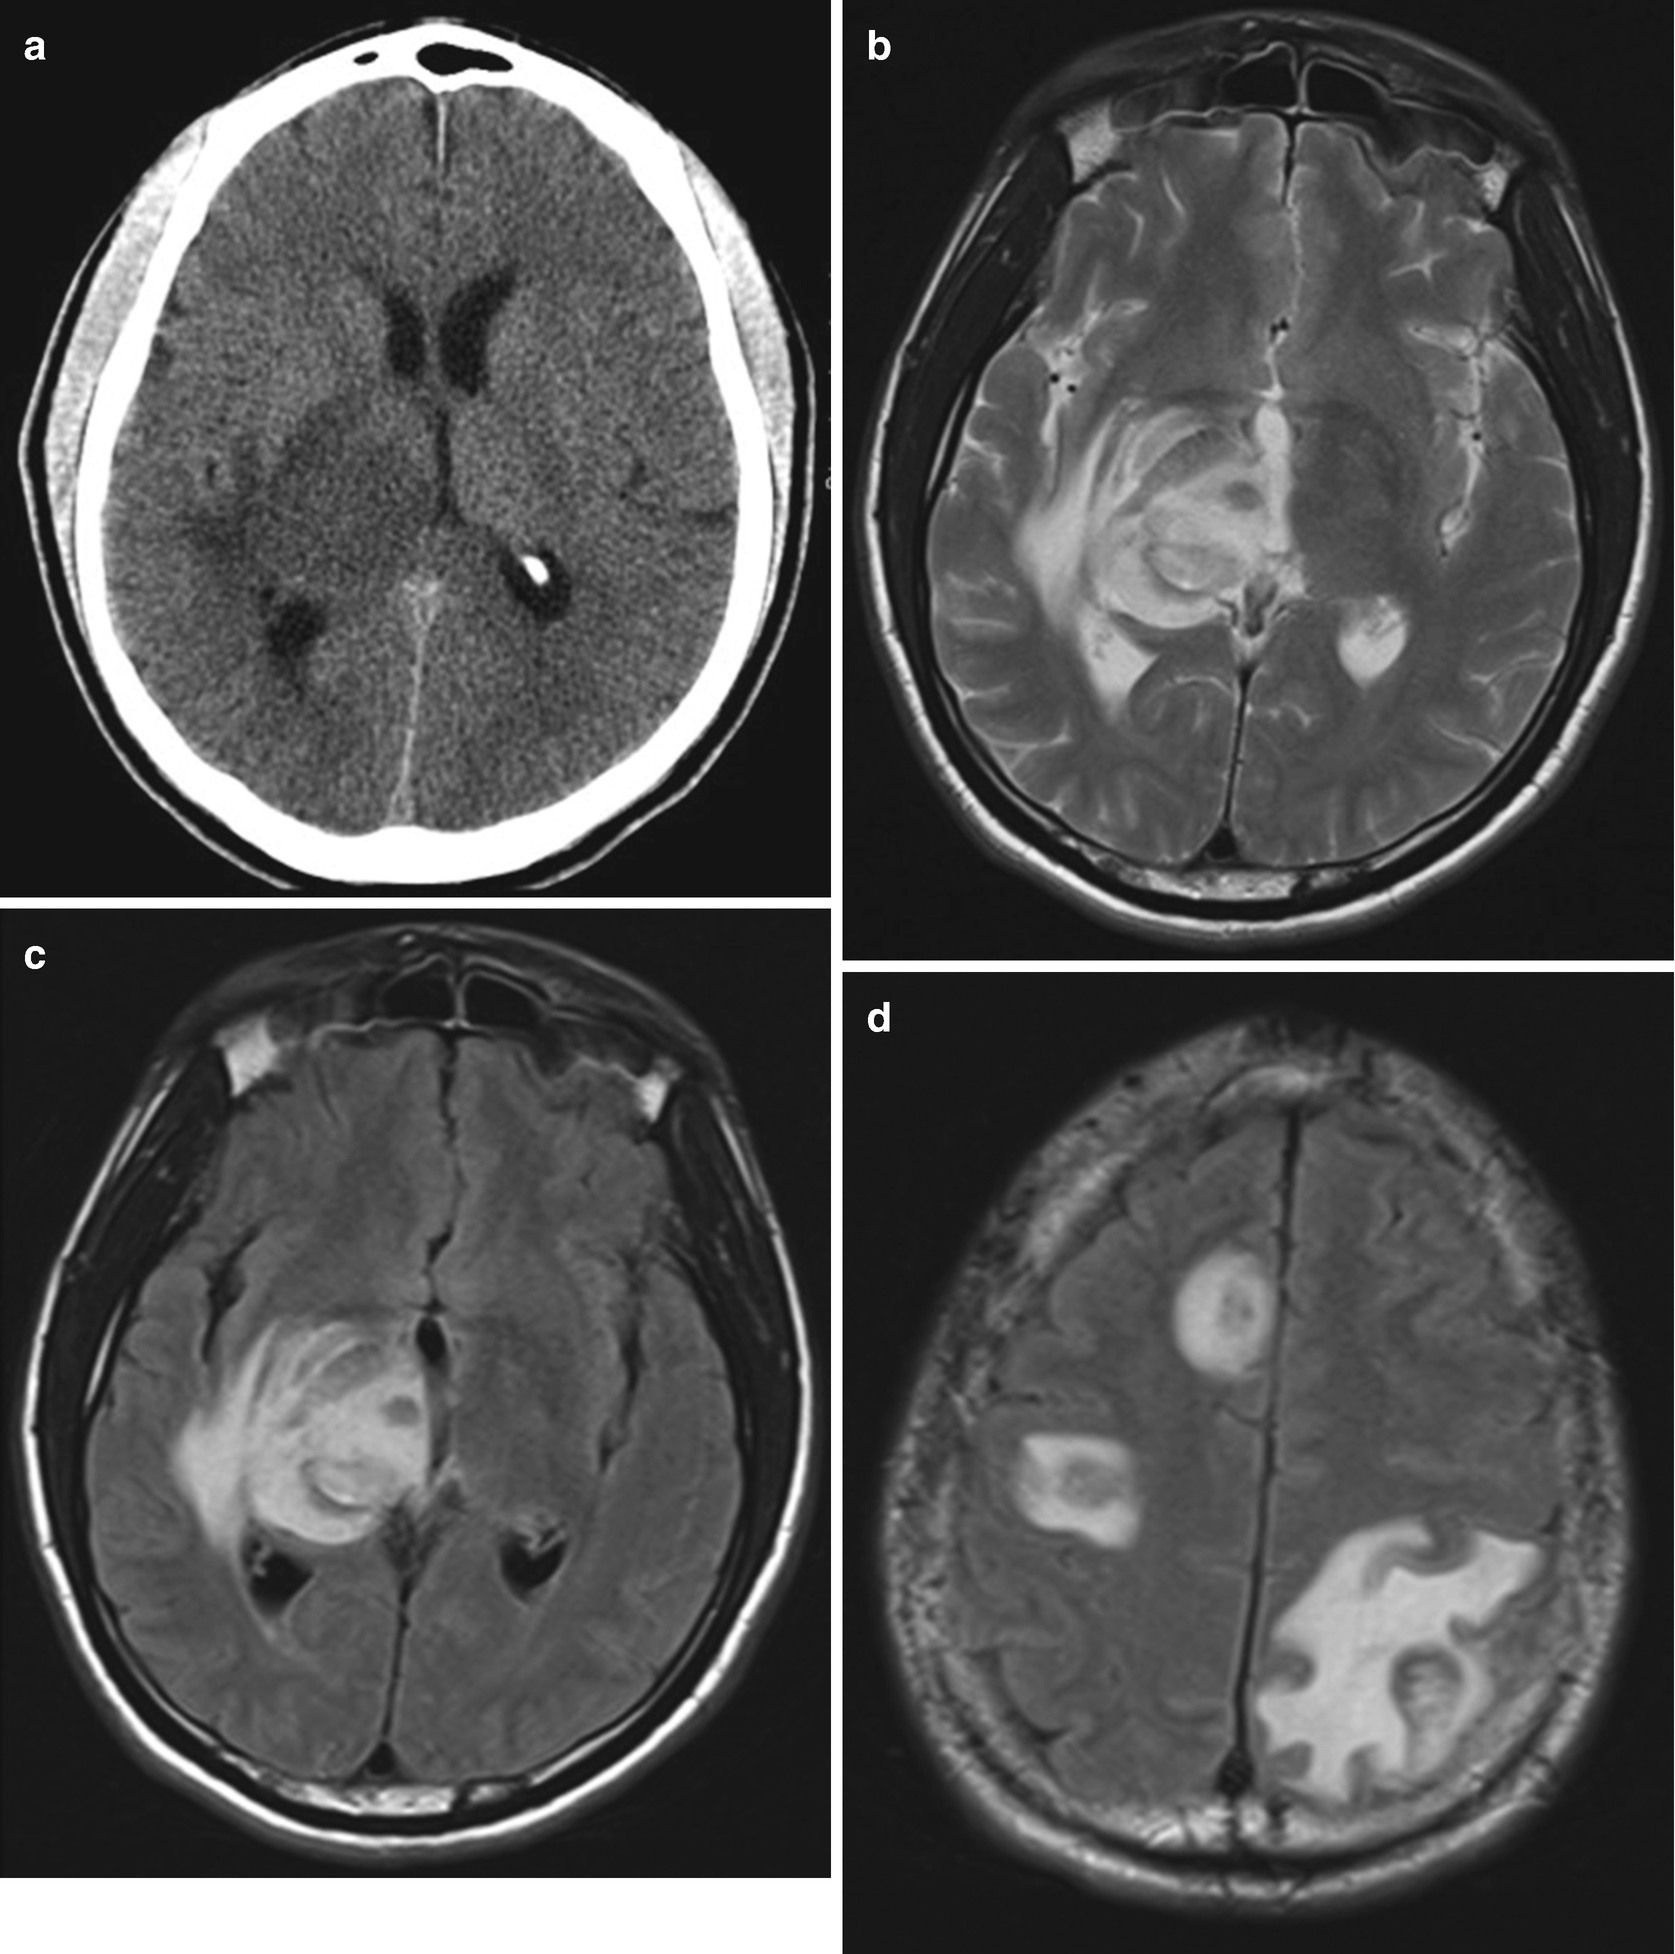

A splenectomiát követõen a bal subphreniumban jelentõs nagyságú, vaskos falú, rekeszes, hypodens (folyadék densitású) képlet (nyilak) látható. A májban látható két apró hypodens képlet a vizsgálattal biztonsággal nem karakterizálható , de valószínű cysta. 10 jobb mellékvese 42x36mm, bal mellékvese 27x29mm homogén hypodens képlet hu érték.

Ovoid hypodens terület jobb oldalon occipitalisan. A bal lebenyben 13, 10,5 mm nagyságú, főleg a vénás fázisban ábrázolódó, jellegzetes halmozást nem mutató hypodens képletek láthatók. A szokottnál kissé nagyobbszámú kis nyirokcsomó paraaorticusan, néhány kis. Tölts le legyűgöző ingyenes képeket képlet témában.